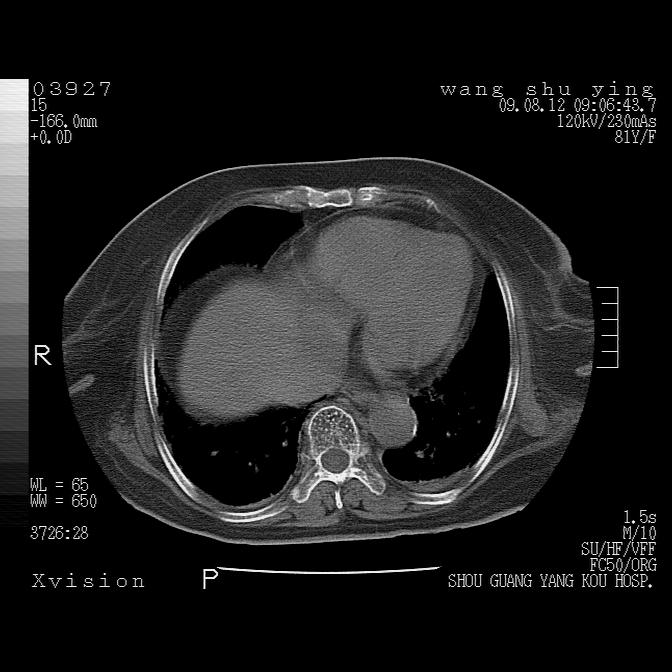

以下是引用帅河马在2009-8-12 12:59:00的发言:[br]两肺感染性病变伴双侧胸膜肥厚。[br]左侧甲状腺腺瘤不除外。[br]腹水+心包积液。[br][br][本贴已被 帅河马 于 2009-8-12 13:14:32 修改过]

以下是引用sdzyy在2009-8-12 18:17:00的发言:[br]两肺感染性病变伴双侧胸膜肥厚。[br]左侧甲状腺腺瘤不除外。[br]腹水+心包积液。[br]支持

以下是引用随光逐影在2009-8-12 19:42:00的发言:[br]1)两肺感染性病变伴双侧胸膜肥厚。2)不排除左侧甲状腺腺瘤。3)肝脏占位性病变;建议行进一步检查。